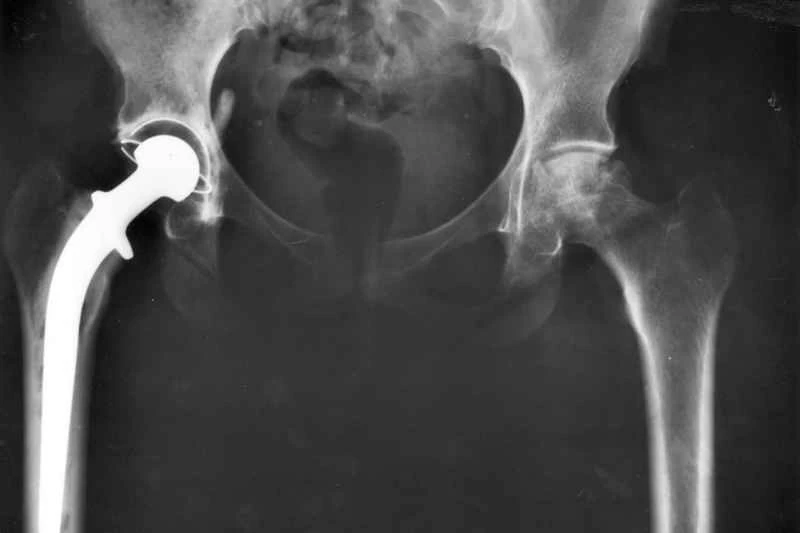

科學研究表明,某些性愛姿勢不會損害你的人工髖關節。

當你爺爺做髖關節置換手術時,你盡量不去想這些問題;但當你裝上人工關節後,一些會晃動髖部的活動就變得有點危險了。比如,跳舞。或者性生活。正如一群勇敢的瑞士研究人員所指出的,在進行全髖關節置換術(即髖關節置換手術)後,「性活動期間假體或骨骼撞擊以及關節不穩定的相對風險」尚不明確。我們也不清楚不同性愛姿勢...